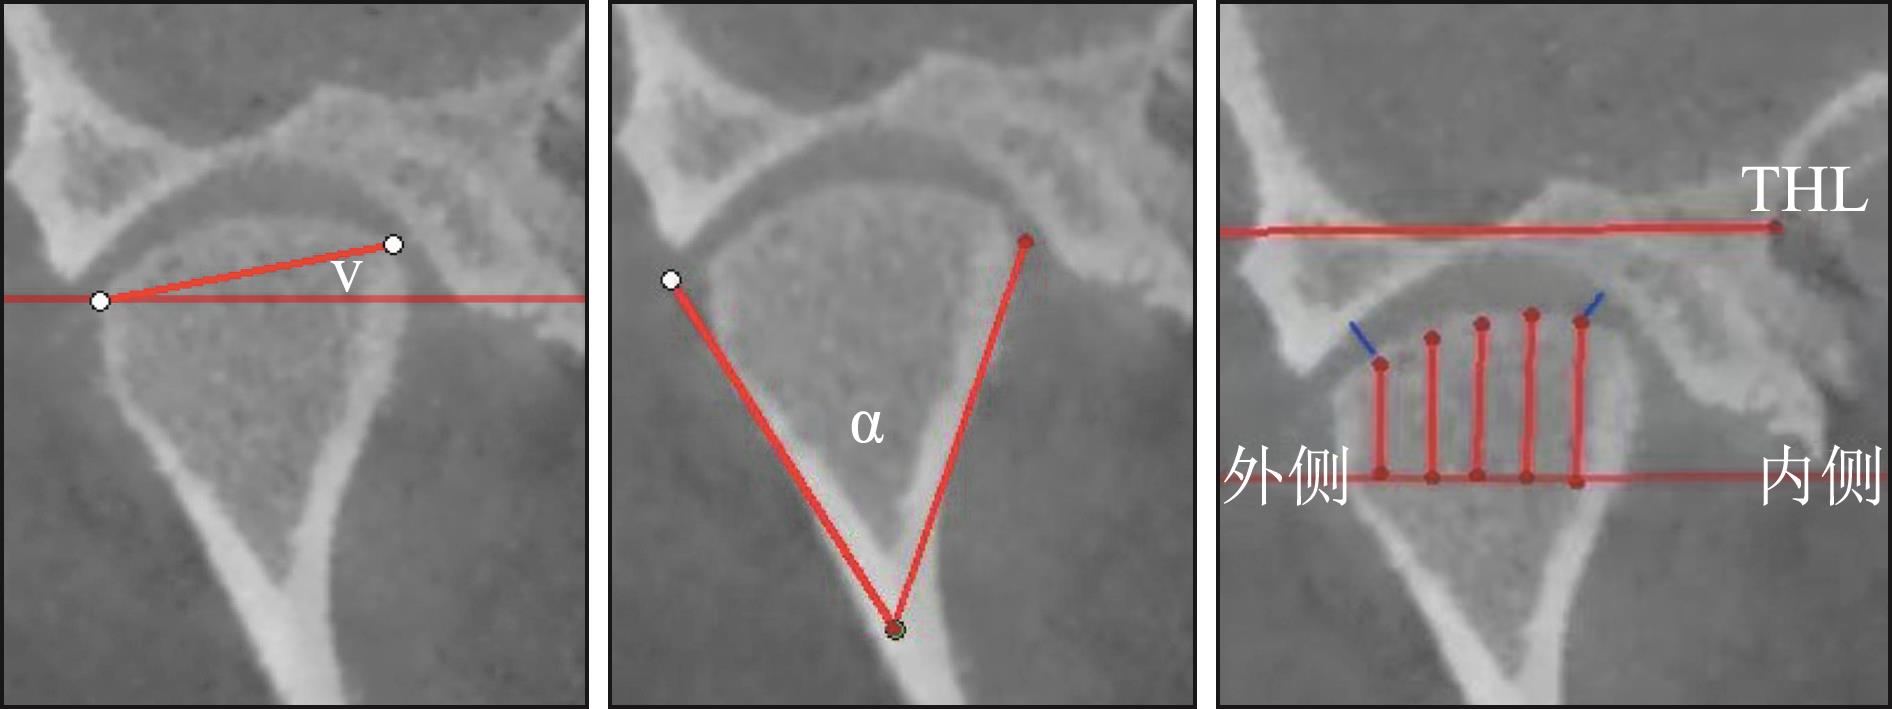

傅开元, 胡敏, 余强, 等. 颞下颌关节紊乱病锥形束CT检查规范及诊断标准的专家共识[J]. 中华口腔医学杂志, 2020, 55(9): 613-616.

Fu KY, Hu M, Yu Q, et al. Experts consensus on cone-beam CT examination specification and diagnostic criteria of temporomandibular disorders[J]. Chin J Stomatol, 2020, 55(9): 613-616.

Ikeda K, Kawamura A. Assessment of optimal condylar position with limited cone-beam computed tomography[J]. Am J Orthod Dentofacial Orthop, 2009, 135(4): 495-501.

|

| [19] |

Kamelchuk LS, Grace MG, Major PW. Post-imaging temporomandibular joint space analysis[J]. Cranio, 1996, 14(1): 23-29.

李晓星, 马博文, 徐鑫宇, 等. 伴偏侧咀嚼颞下颌关节骨关节炎患者1年随访的CBCT研究[J]. 口腔颌面修复学杂志, 2025, 26(1): 42-49.

Li XX, Ma BW, Xu XY, et al. CBCT study of patients with temporomandibular joint osteoarthritis accompanied by lateral chewing for 1 year follow-up[J]. Chin J Prosthodont, 2025, 26(1): 42-49.